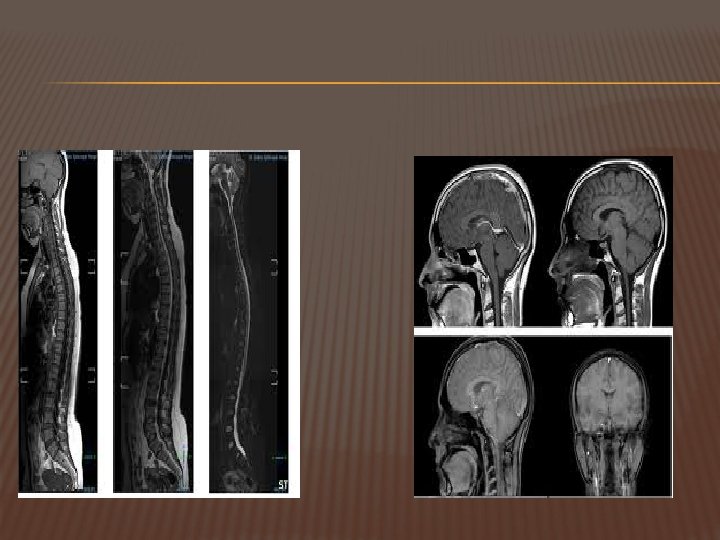

MRI (MAGNETIC RESONANCE IMAGING ) suatu alat diagnostik mutahir untuk memeriksa dan mendeteksi tubuh dengan menggunakan medan magnet dan gelombang frekuensi radio, tanpa operasi, penggunaan sinar X ataupun bahan radioaktif.

MANFAAT MRI Deteksi dini kelainan otak dan syaraf tulang belakang Deteksi dini dari kasus-kasus stroke Deteksi kelainan otot sendi dan sumsum tulang Deteksi dini kelainan organ reproduksi wanita Pemeriksaan saluran empedu (MRCP) Pemeriksaan pembuluh darah (MRA)

KELEBIHAN MRI Beberapa faktor kelebihannya adalah kemampuan dalam membuat potongan koronal, sagital, aksial dan oblik tanpa banyak memanipulasi posisi tubuh pasien sehingga sangat sesuai untuk diagnostik jaringan lunak.